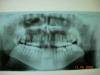

Верхняя микрогнатия

Диагноз: Перекрёстный левосторонний прикус, скученое положение резцов нижней челюсти, смещение косметического цэнтра верхнего зубного ряда, раннее удоление 26.

План лечения:. интенсивный нёбный разширитель( говорит даже разрывает нёбный шов). направление на удоление 18, 38, 48. и ткаже, дэймоны Нужно уменьшить зубной ряд справо верх и уменьшить зубные ряды снизу.

Диагноз: Верхняя микрогнатия.

Рекомендовано - расширить верхнюю челюсть ортодонтическим способом с постоновкой прикуса в ортогнатическое положение. В хирургическом лечение не нуждаеться.

ТРГ ОПТГ

Расширить челюсть взрослому пациенту можно, для этого применяют спец. винты, удлинить челюсть можнотолько хирургической коррекцией. Можно изменить длину зубного ряда, это у взрослых пациентов достигается методом удаления, либо изменением наклона зубов. Я соглашусь со вторым ортодонтом, явных показаний к хирургической коррекции у Вас нет.